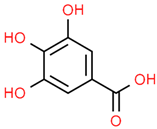

| 7 | Gallic acid | 370 | C7H6O5 | 170.12 | C1=C(C=C(C(=C1O)O)O)C(=O)O |  |